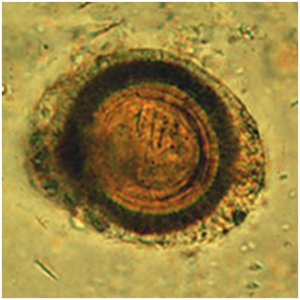

البيضة :

بيضة

وهي تشبه بيضة الشريطية العزلاء من الناحية الشكلية ( رغم أن تخطيطاتها الشعاعية أرق و أكثر عدداً ومحيطها أكثر استدارة و حجمها أكبر و لكن لا يمكن تمييز ذلك بالمجهر الضوئي ) ولكن تختلف عنها بميزة هامة جداً بأنها خامجة للإنسان . الكيسة المذنبة الخلوية Cysticercus celulosae: وهي رقيقة الجدار نصف شفافة و تقيس 10 × 5 مم وتكون بلون أبيض براق وفيها سائل رائق و داخلها طليعة رؤيس منغلف له صفين من أشواك يبدو بشكل منطقة كثيفة في احد جوانب الكيسة و يمكنه البقاء حياً لمدة خمس سنوات .